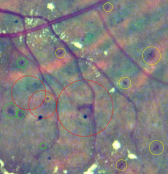

Finally, qualitative results for a randomly selected image in the DIARETDB1 test set are depicted in Figure 10. Green circles are detected lesions according to the ground truth labeling provided in the data set, while yellow circles correspond to lesions detected by our method but that are not labeled in the ground truth. Finally, red circles surround the lesions that were manually annotated as true lesions but were ignored by the method. Qualitatively, many of the yellow circles appear to be microaneurysms or hemorrhages that were not detected during manual labeling due to their subtle appearance in the original RGB image.

Detailed regions of the embeddings are depicted in Figure 15. This allows better visualization of particular scenarios such as the patches around the true red lesions, the false positive candidates located in the vascular structures, the artifacts due to speckles of dirt in the lens–which are typical of the images in DIARETDB1–and the false detections within the optic disc. In general, it is possible to observe that CNN features are able to better characterize the orientation and the visual appearance of the true lesion candidates, while the hand crafted features can detect the less obvious lesions under low contrast conditions. The ability of the CNN features to discriminate orientations are more evident when dealing with vascular structures. The hand crafted approach, by contrast, is only able to capture the overall size of the vessels and their intensity properties. When combining both strategies, the main advantages of each of them are maintained. The robustness against artifacts is evident for both the deep learning based and the hand crafted features, as these false positive candidates are grouped together into separate clusters from the true lesions. A similar behavior is observed when dealing with false candidates within the optic disc area.